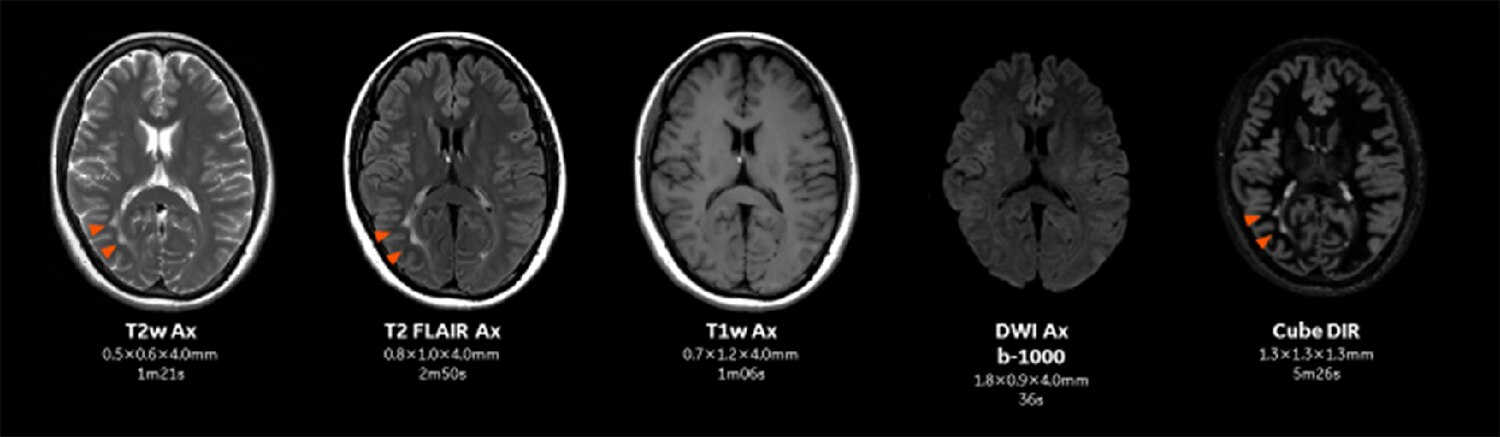

Figure. 1

SIGNA Pioneer 3.0T AIR IQ Editionにおける頭部MR検査のプロトコル。従来より薄いスライスで短時間に撮像が可能となっている。

従来の頭部MRのプロトコルでは全脳を5mmで行っていたが、AIR™ IQ Editionの導入によりスライス厚を3-4mmに変更した。従来のプロトコルより薄いスライスで撮像することにより、部分容積効果が軽減する。

今までMRIの診断ではCTとは異なり部分容積効果を無意識に許容していたが、Thin slice化によって想定以上の診断能向上効果を感じている。またThin slice化により全脳をカバーするのにスライス数が増加しているが、加算回数を減らしたり、パラレルイメージングのファクターを上げたりすることによって従来のプロトコルより短時間で撮像を行うことが可能となっている(Figure.1)。